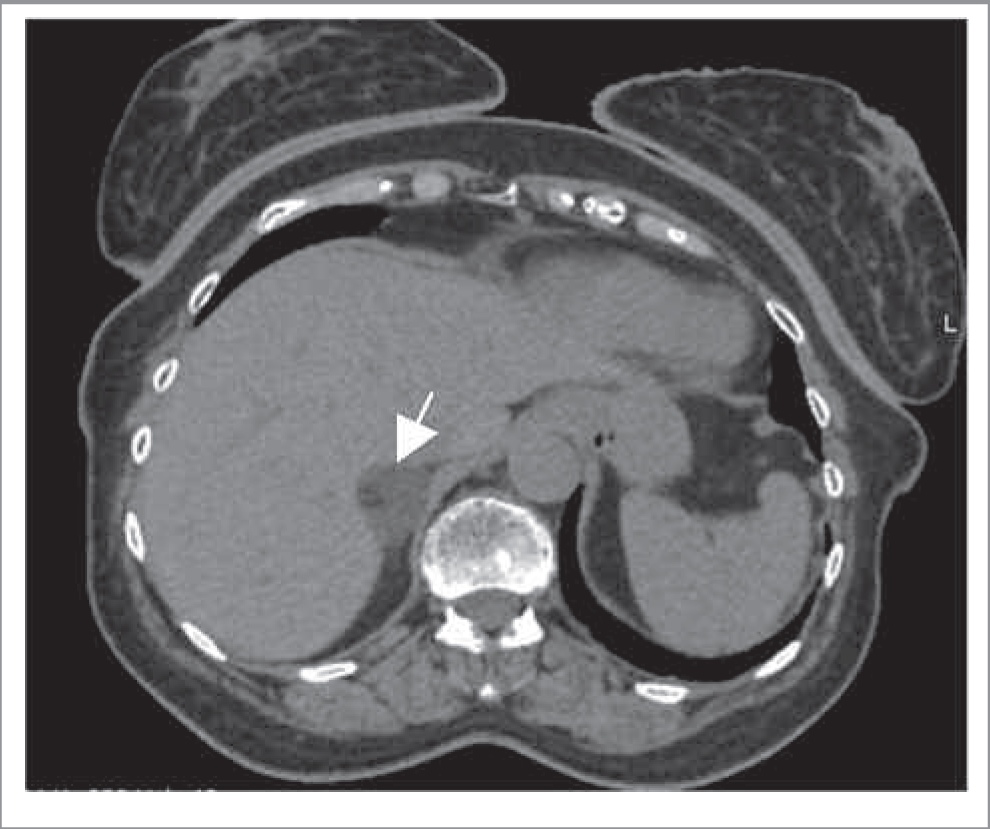

Как правило, АКР представляет собой крупное образование (от 2 до 40 см, в среднем 11–12 см) с неровными нечеткими контурами, повышенной плотности (более 10 ед. Н). При болюсном контрастном усилении образование умеренно неоднородно накапливает контрастный препарат со слабым его вымыванием в ОФ. Для данного образования характеры зоны некроза и кровоизлияний, а также кальцинаты, которые встречаются в 30% случаев [20]. При контрастировании возможно обнаружение тонкого капсулоподобного ободка контрастирования (рис. 7) [21]. Необходимо учитывать, что АКР также может быть выявлен в структуре таких доброкачественных образований, как аденомы (в структуре коллизионной опухоли); рис. 8.

Рис. 7. МСКТ, аксиальная проекция. Рак надпочечника. КТ-изображения в аксиальной проекции: а – НФ; б – АФ; в – ВФ; г – ОФ. В теле правого надпочечника определяется овальной формы образование (стрелка) с четкими ровными контурами, неоднородной структуры за счет наличия кальцинатов по периферии.

Рис. 8. МСКТ, аксиальная проекция. Коллизионная опухоль правого надпочечника (рак в структуре аденомы). КТ-изображения в аксиальной проекции: а – НФ; б – АФ; в – ВФ; г – ОФ. В правом надпочечнике определяется округлое образование (стрелка) пониженной плотности с четкими ровными контурами, неоднородной структуры за счет наличия центрально расположенного мягкотканного включения, интенсивно накапливающего контрастный препарат, со слабым его вымыванием в ВФ и ОФ.

Чаще поражается левый надпочечник, в то время как двустороннее поражение встречается менее чем в 10% случаев [20]. Для АКР характерны признаки злокачественности: инвазивный рост с вовлечением окружающих структур и органов или метастазы. Вовлечение почечной вены (9–19% наблюдений) чаще встречается при опухоли правого надпочечника и проявляется распространением опухоли в просвете данной вены, далее в нижней полой вене до правого предсердия [20]. Метастазы наиболее часто поражают легкие, печень, лимфатические узлы и кости.